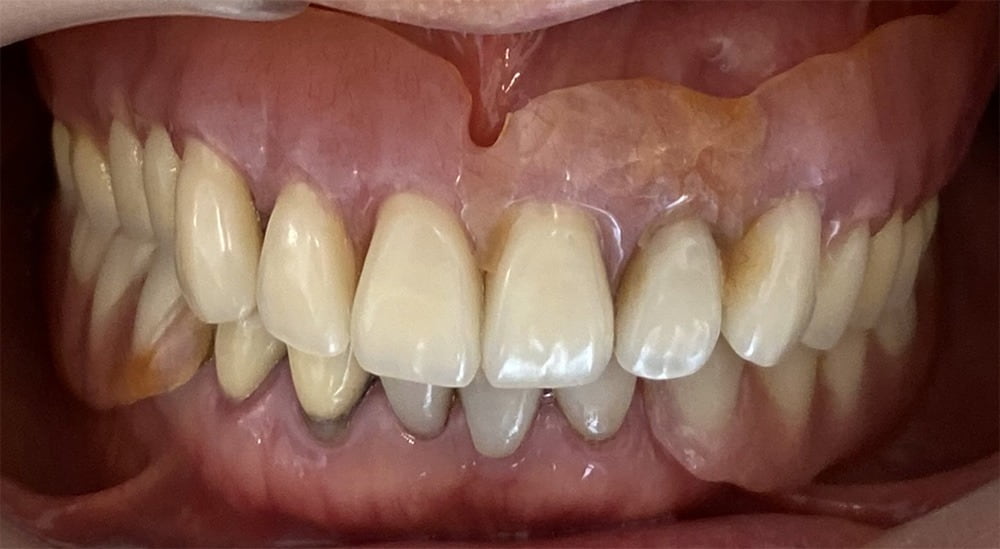

口腔内(正面)

Before